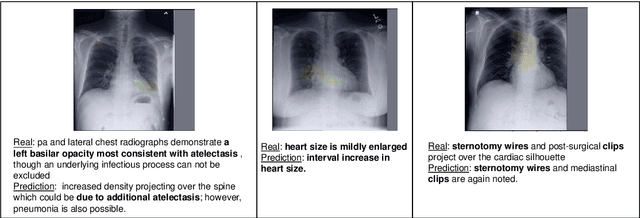

Abstract:Radiology report generation aims at generating descriptive text from radiology images automatically, which may present an opportunity to improve radiology reporting and interpretation. A typical setting consists of training encoder-decoder models on image-report pairs with a cross entropy loss, which struggles to generate informative sentences for clinical diagnoses since normal findings dominate the datasets. To tackle this challenge and encourage more clinically-accurate text outputs, we propose a novel weakly supervised contrastive loss for medical report generation. Experimental results demonstrate that our method benefits from contrasting target reports with incorrect but semantically-close ones. It outperforms previous work on both clinical correctness and text generation metrics for two public benchmarks.

Abstract:Automatic medical image report generation has drawn growing attention due to its potential to alleviate radiologists' workload. Existing work on report generation often trains encoder-decoder networks to generate complete reports. However, such models are affected by data bias (e.g.~label imbalance) and face common issues inherent in text generation models (e.g.~repetition). In this work, we focus on reporting abnormal findings on radiology images; instead of training on complete radiology reports, we propose a method to identify abnormal findings from the reports in addition to grouping them with unsupervised clustering and minimal rules. We formulate the task as cross-modal retrieval and propose Conditional Visual-Semantic Embeddings to align images and fine-grained abnormal findings in a joint embedding space. We demonstrate that our method is able to retrieve abnormal findings and outperforms existing generation models on both clinical correctness and text generation metrics.